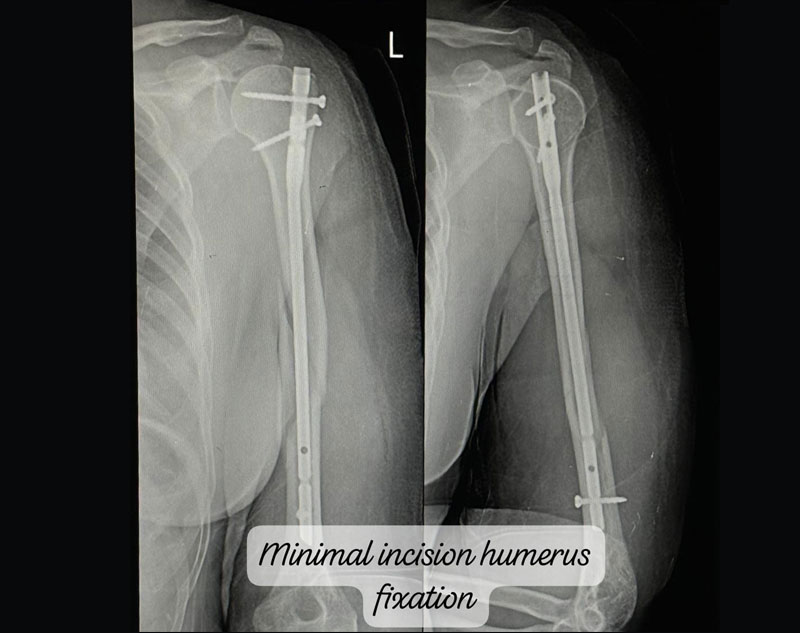

Treatment for complex trauma requires a multidisciplinary approach, including surgical intervention, internal/external fixation, and sometimes reconstruction of damaged tissues.